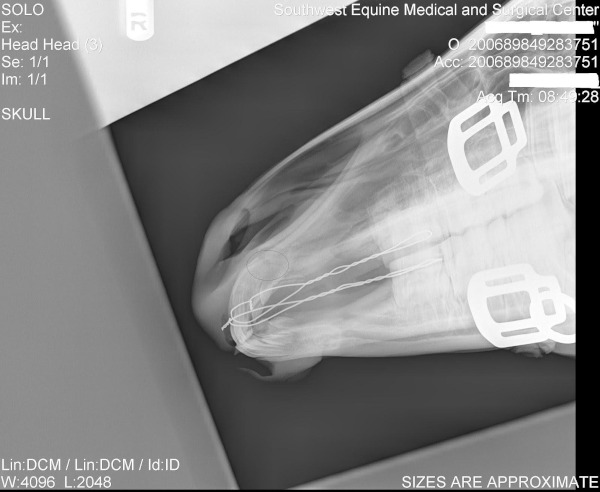

Upon arrival to Southwest Equine, Jawbreaker and the mare were both a little groggy since they had been sedated for the trailer ride.  Oral evaluation revealed that the incisive bone was visibly fractured.  It was also noted that large portions of the hard palate and other surrounding soft tissues were reflected away from the boney margins.  Radiographs (X-Rays) were taken to determine the extent of the fracture.   Radiographs showed that the fracture was complete (all the way through the bone), but did not indicate that any other fractures were present.  The owners elected for surgical correction of the fracture at that time.

Jawbreaker was prepared for surgery and the mare was sedated and placed in a stall while he was in surgery.  During surgery, the fracture and soft tissue wounds were cleaned of all dirt and debris.  The fracture was reduced (ie the bones were put back in a normal position) and the incisors were aligned, fixation wires were placed to hold the bones in their proper place.  “Wiring” was performed by drilling between the upper 2nd and 3rd premolar teeth on both sides to allow for placement of an 18 gauge wire.  These wires were then brought forward and were guided through the gums on midline, just above the incisors.  The wires were manually tightened to provide fracture stability.  The soft tissues were then sutured together to regain normal oral anatomy.  The fixation wires were then coated with methylmethacrylate to further enhance their strength.  Jawbreaker recovered from surgery uneventfully.

After surgery Jawbreaker was treated with injectable antibiotics for three days as well as IV flunixin meglumine (Banamine) for 5 days.  The Banamine was then discontinued and Jawbreaker was switched to oral antibiotics for another 6 days.  Jawbreaker and the mare were fed soaked alfalfa pellets.  This was done to prevent the teeth from grinding on the fixation wires as much as possible.  Jawbreaker had a great appetite and was able to nurse and eat normally post-operatively.  Radiographs were taken ten days after surgery.  Radiographs showed that at that time the fracture was healing, but still visible and the fixation wires were still intact.  Jawbreaker continued to do well and was sent home with instructions to repeat radiographs in 2-3 weeks.

Four weeks after surgery, radiographs were repeated of Jawbreaker’s fracture.  These radiographs showed that the fracture line was remodeling, however still visible and that the fixation wires were still intact.  At that time it was recommended to recheck in one month to re-asses the fracture.